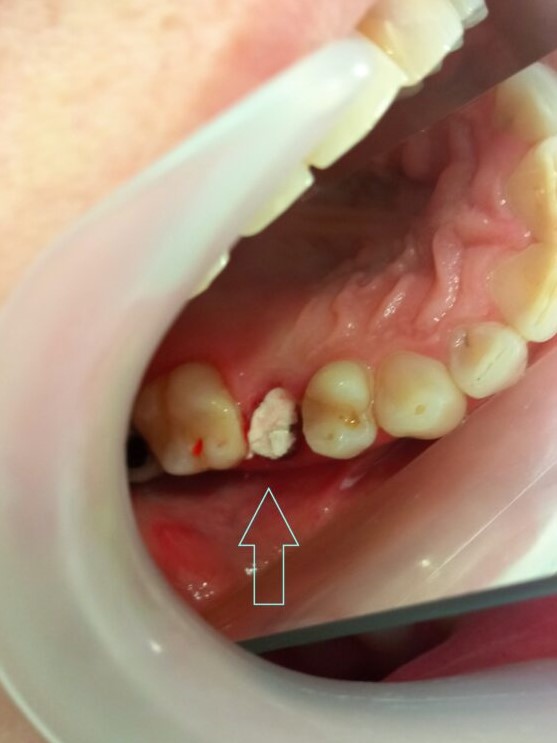

Αρχική κλινική εικόνα του παλιού σπασμένου σφραγίσματος